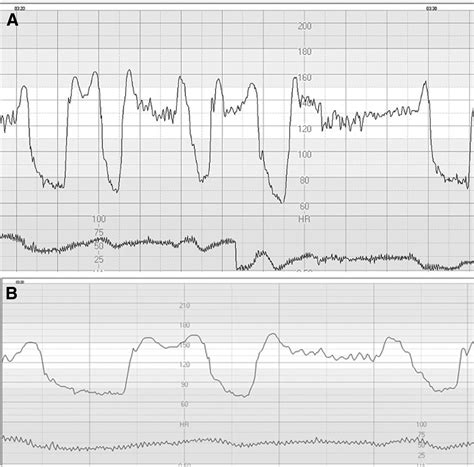

When healthcare providers look at a fetal heart tracing strip, they are analyzing several specific components. The goal is to determine if the heart rate pattern is "reassuring" (normal) or "non-reassuring" (abnormal). Key elements include:

• Baseline Rate: The average heart rate of the fetus, excluding accelerations and decelerations. A normal range is generally between 110 and 160 beats per minute (bpm).

• Variability: This refers to the minor fluctuations in the baseline heart rate. Good variability is a sign of a healthy, functioning autonomic nervous system in the fetus.

• Accelerations: Temporary increases in the heart rate, usually in response to fetal movement. These are excellent signs of fetal well-being.

• Decelerations: Temporary decreases in the heart rate. Some are normal (early decelerations), while others might suggest the baby is struggling (late or variable decelerations).

⚠️ Note: Not all decelerations indicate distress. Early decelerations, which mirror contractions, are often caused by head compression and are usually considered a normal, harmless part of labor.